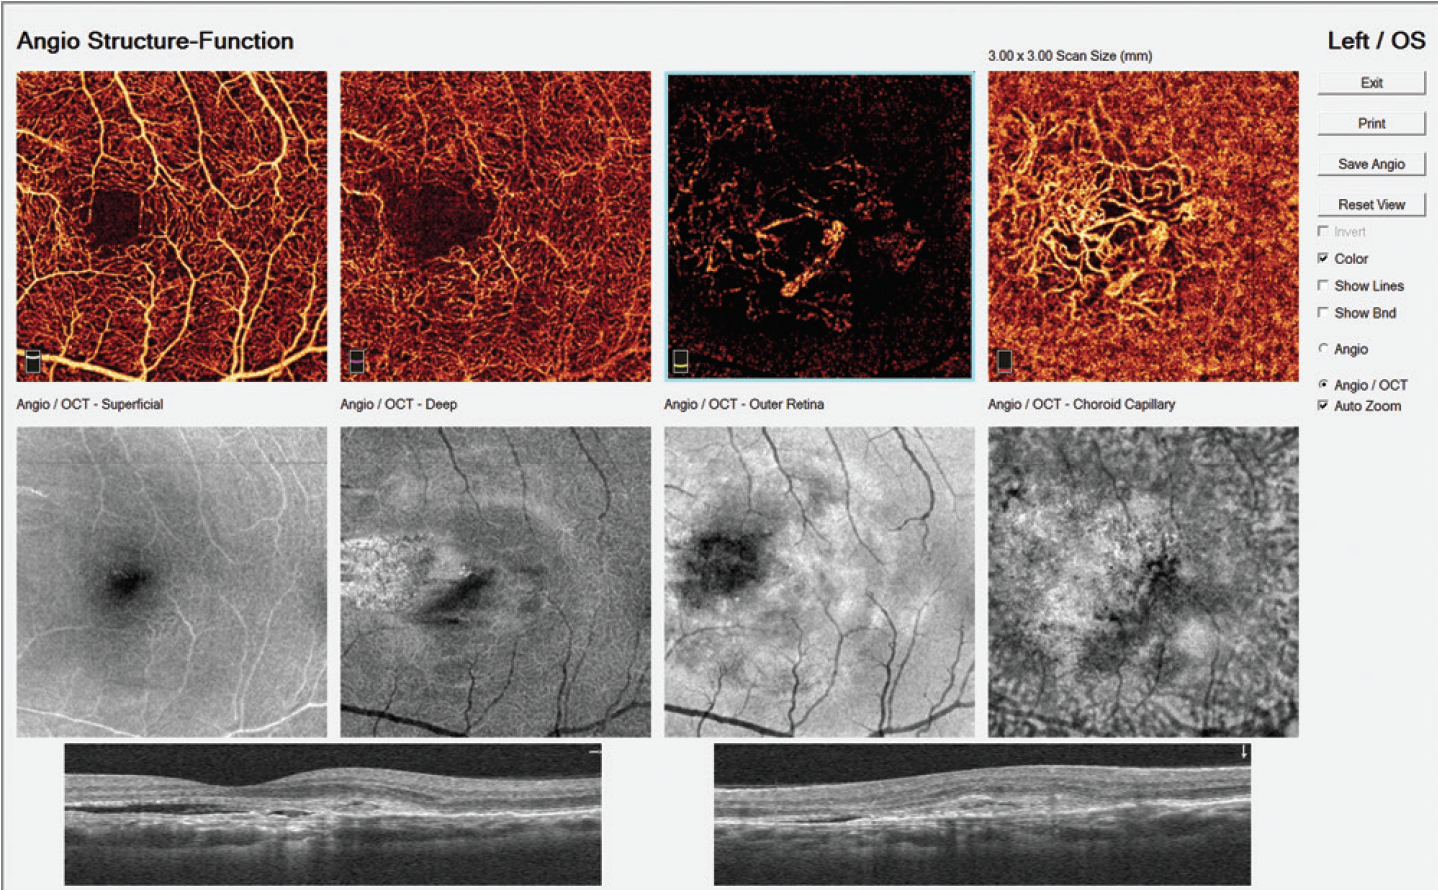

Figure 7. Typical AngioVue report in type 1 CNV. The cross-sectional OCT shows irregular subretinal fluid with thickened photoreceptor outer segments. Hyperreflective material is evident at the fluid site with irregular retinal pigment epithelium. OCTA shows normal texture of the vascular retina (superficial and deep capillary plexuses). A large, irregular neovascular network is evident in the choriocapillaris layer.

Figure 8. Cross-sectional OCT in type 2 CNV reveals CME, white intraretinal dots, and pseudostratified substance below the retina (A, right-hand images). OCTA scans show normal texture of the vascular retina in the superficial (B) and deep (C) capillary plexuses. The avascular zone (D)reveals a large neovascular wheel-shaped network with a central main mature vessel surrounded by growing loops.

In type 1 CNV secondary to AMD (Figure 7), the new vessels initially appear under the pigment epithelium, and no flow is seen in the avascular outer retina. The neovascular network is often extensive, with high flow and varied morphology (Video 2). New vessels may appear in a variety of shapes, including a medusa head, coral reef, bicycle wheel, fan, and dead tree. The tangled network generally contains filaments, loops, and a vascular arcade. The vascular complex almost always has a feeder trunk or a bundle of feeder vessels.

In type 2 CNV (Figure 8) new vessels are always located above the retinal pigment epithelium, but they also spread deeply into the outer retinal avascular area. The flow is high; however, the morphology is less varied than in type 1 CNV, with the morphology most frequently appearing as bicycle wheel or fan-like shapes (Video 3). The neovascular network area is smaller than in type 1 CNV.